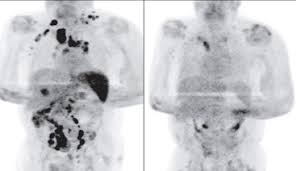

Diagnostic testing is used to detect the cancer's stage, which helps the doctor determine an appropriate course of treatment. Lymphoma a group of blood cancers that develop in the lymphatic system. Lymphoma staging is identifying where the disease is located and the potential areas of your body it may have spread to. These cancers change the way blood cells behave and how well they work. Leukemia and lymphoma are both forms of blood cancer, but they affect the body in different ways. Many types of lymphoma exist. But it is very rare, accounting for about 2 percent of all lymphoma diagnoses. There are two main types of lymphoma, which spread and are treated differently: Which lymphoma treatments are right for you depends on the type and stage of your disease, your overall health, and your preferences. The two main kinds of lymphoma are— hodgkin lymphoma, which spreads in an orderly manner from one group of lymph nodes to another. The lymphatic system includes the lymph nodes (lymph glands), spleen, thymus gland and bone marrow. These cells are in the lymph nodes, spleen, thymus, bone marrow, and other parts of the body. Lymphoma is a cancer of the lymph (or lymphatic) system.

Hodgkin lymphoma can develop anywhere in the body where lymphocytes are found. Those affected may feel tired or be itchy. Diagnostic testing is used to detect the cancer's stage, which helps the doctor determine an appropriate course of treatment. Lymphoma is the most common type of blood cancer. Lymphomas refers to types of cancer that begin in the lymphatic system (the various lymph glands around the body) when abnormal white blood cells grow. Lymphoma is a group of blood malignancies that develop from lymphocytes (a type of white blood cell). This is usually in the neck, armpit or groin. But it most often begins in lymph nodes in the chest, neck or under the arms. It develops in lymphocytes, which are a type of white blood cell. Lymphoma is a general term for cancers that start in the lymph system (the tissues and organs that produce, store, and carry white blood cells that fight infections). These cells are in the lymph nodes, spleen, thymus, bone marrow, and other parts of the body. When you're looking for information about lymphoma, make sure you know which type you want to know about. Symptoms from lymphoma in the chest when lymphoma starts in the thymus or lymph nodes in the chest, it may press on the nearby trachea (windpipe), which can cause coughing, trouble breathing, or a feeling of chest pain or pressure.